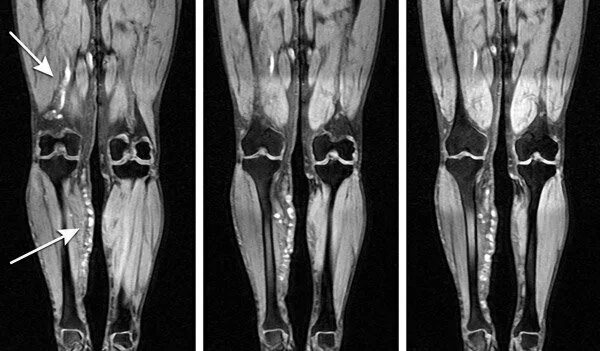

Кт тканей